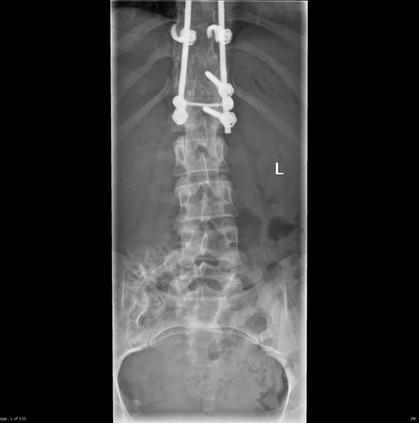

In this study, we aim to initiate the development of Radiology Foundation Model, termed as RadFM.We consider the construction of foundational models from the perspectives of data, model design, and evaluation thoroughly. Our contribution can be concluded as follows: (i), we construct a large-scale Medical Multi-modal Dataset, MedMD, consisting of 16M 2D and 3D medical scans. To the best of our knowledge, this is the first multi-modal dataset containing 3D medical scans. (ii), We propose an architecture that enables visually conditioned generative pre-training, allowing for the integration of text input interleaved with 2D or 3D medical scans to generate response for diverse radiologic tasks. The model was initially pre-trained on MedMD and subsequently domain-specific fine-tuned on RadMD, a radiologic cleaned version of MedMD, containing 3M radiologic visual-language pairs. (iii), we propose a new evaluation benchmark that comprises five tasks, aiming to comprehensively assess the capability of foundation models in handling practical clinical problems. Our experimental results confirm that RadFM significantly outperforms existing multi-modal foundation models. The codes, data, and model checkpoint will all be made publicly available to promote further research and development in the field.